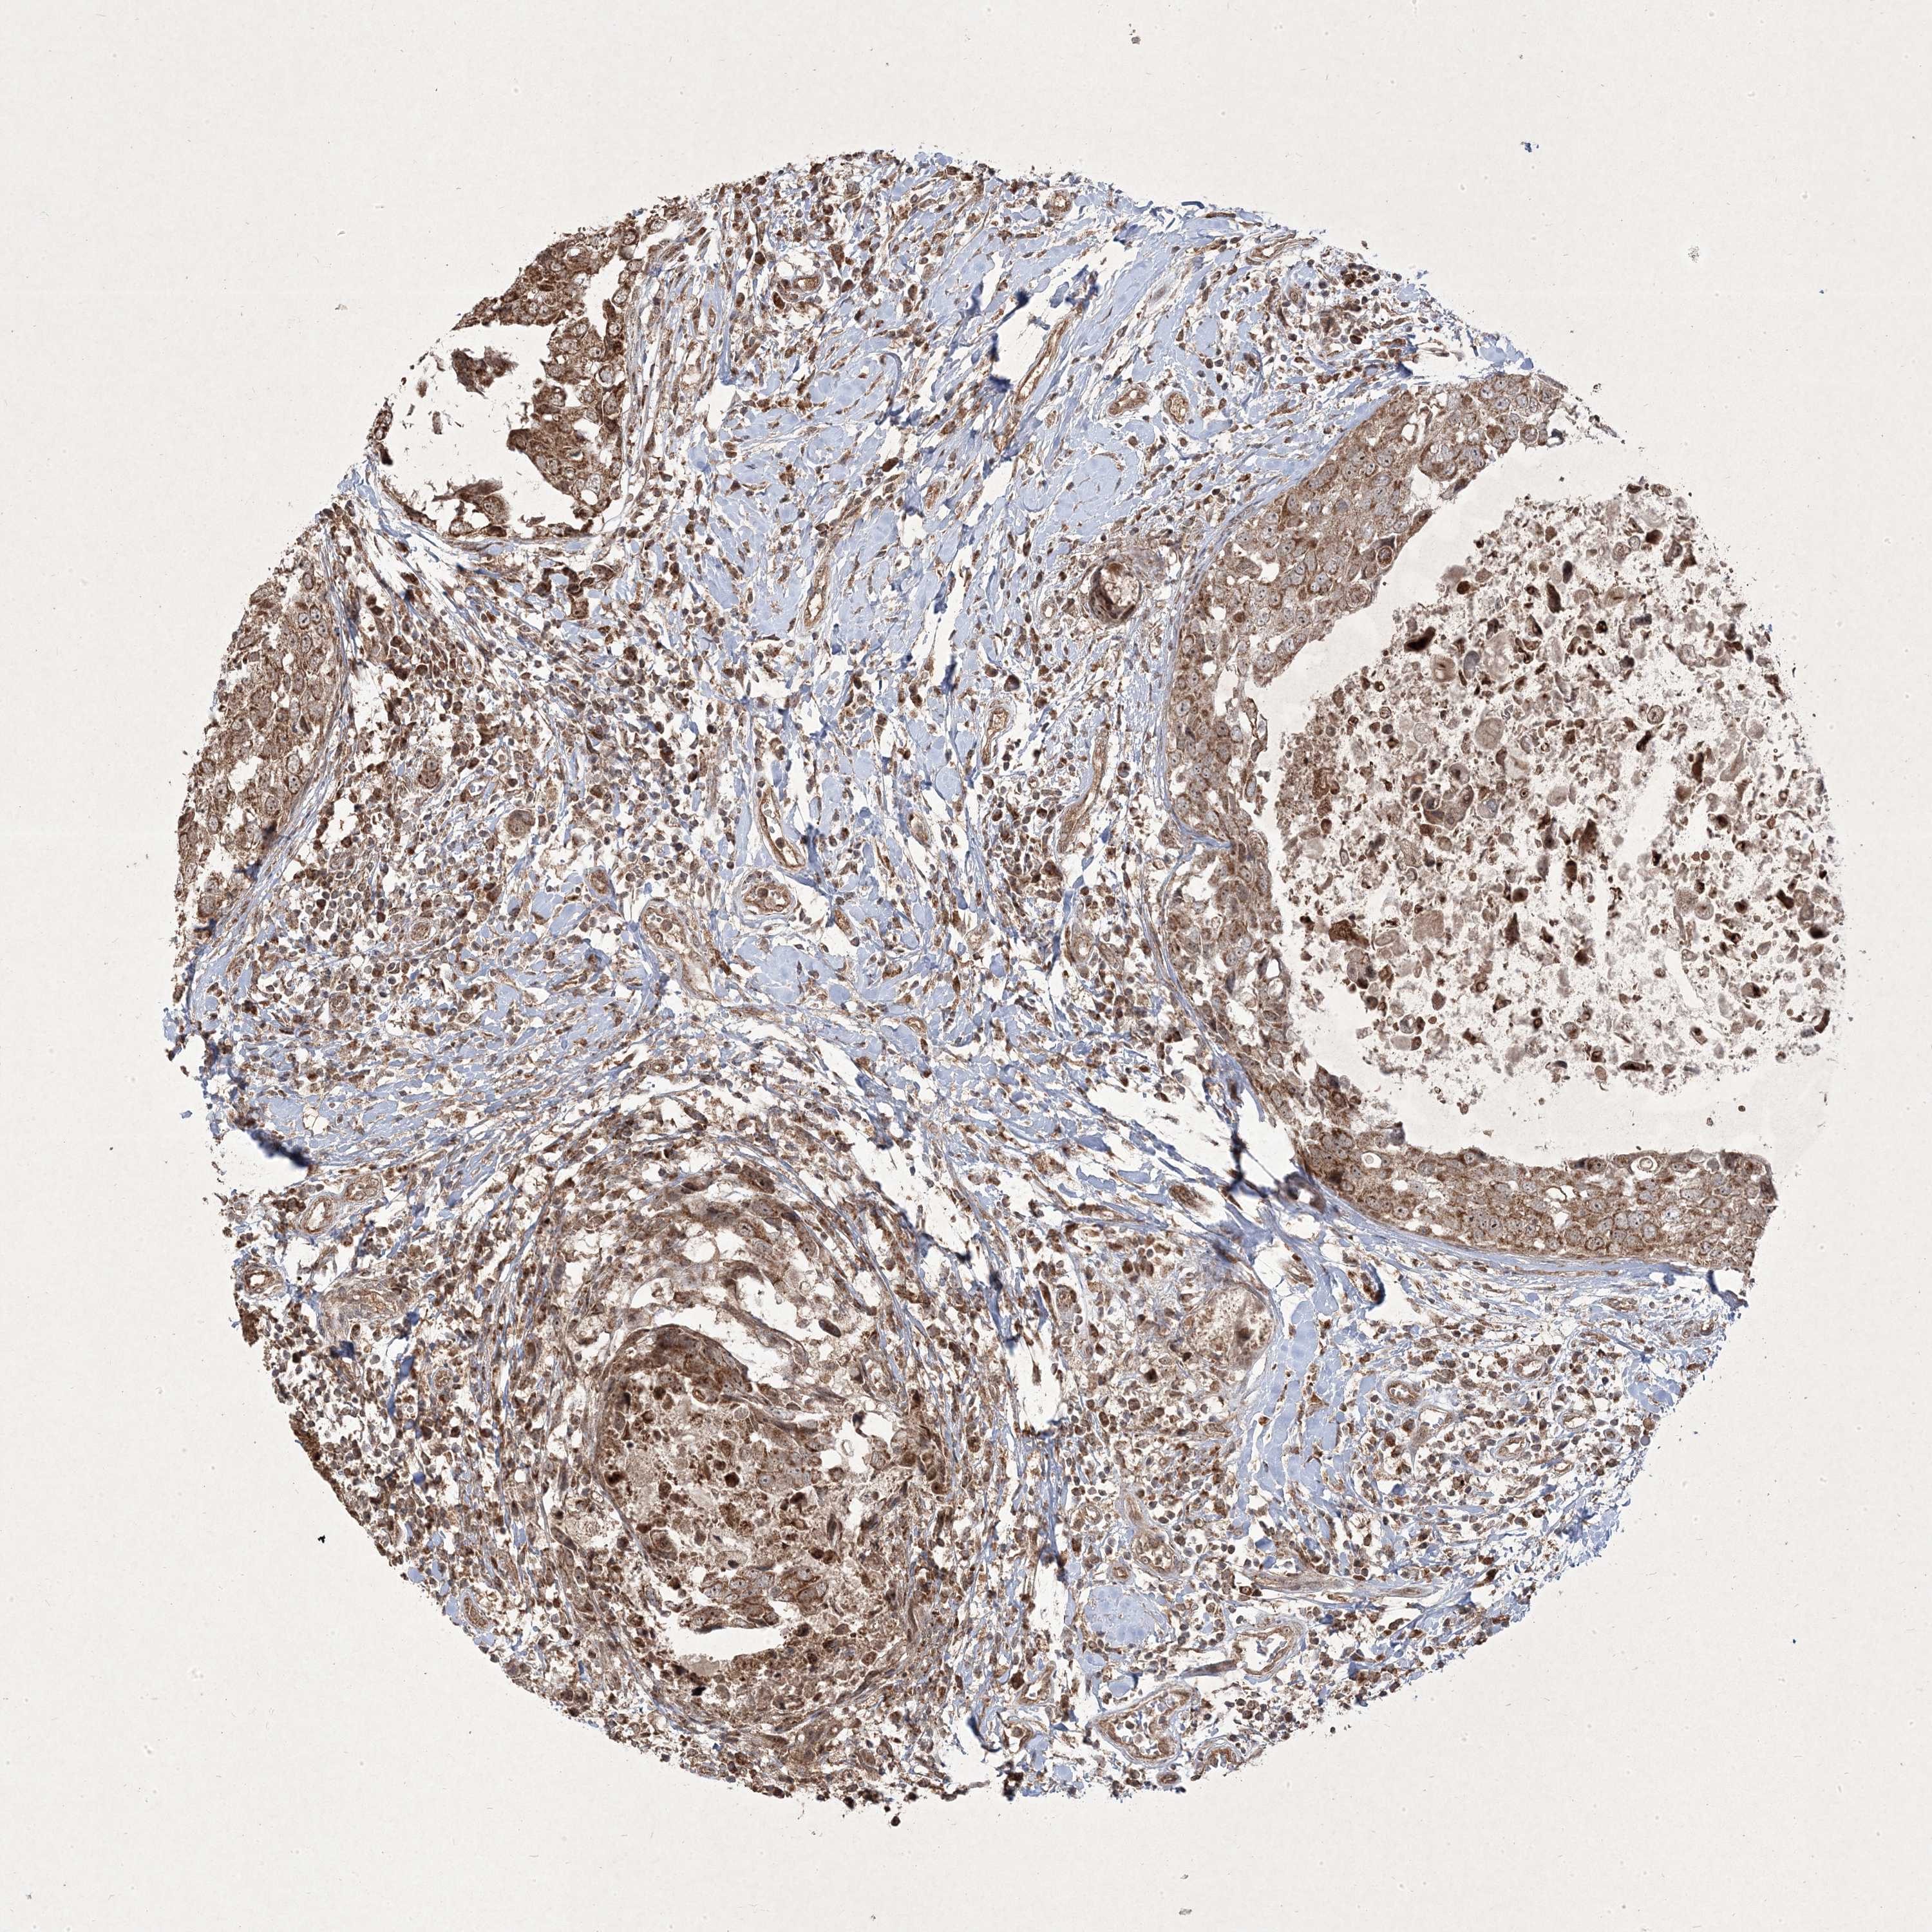

CANCER BREAST CANCER Show tissue menu

BRCA TCGA BRCA VALIDATION PROTEIN EXPRESSION